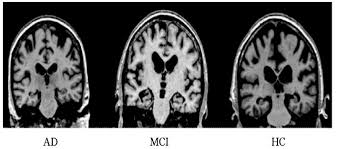

阿尔茨海默病 MRI 预处理数据集 (128 x 128) 数据是从多个网站/医院/公共存储库收集的。 该数据集由预处理的 MRI(磁共振成像)图像组成。 所有图像的大小均调整为 128 x 128 像素。 该数据集有四类图像。 该数据集总共包含 6400 张 MRI 图像。 类别 - 1:轻度痴呆(896 张图片) 类别 - 2:中度痴呆(64 张图片) 类别 - 3:非痴呆(3200 张图片) 类别 - 4:极轻度痴呆(2240 张图片)

该数据集由预处理的 MRI(磁共振成像)图像组成。

该数据集有四类图像。

该数据集总共包含 6400 张 MRI 图像。

类别 - 1:轻度痴呆(896 张图片)

类别 - 2:中度痴呆(64 张图片)

类别 - 3:非痴呆(3200 张图片)

类别 - 4:极轻度痴呆(2240 张图片)